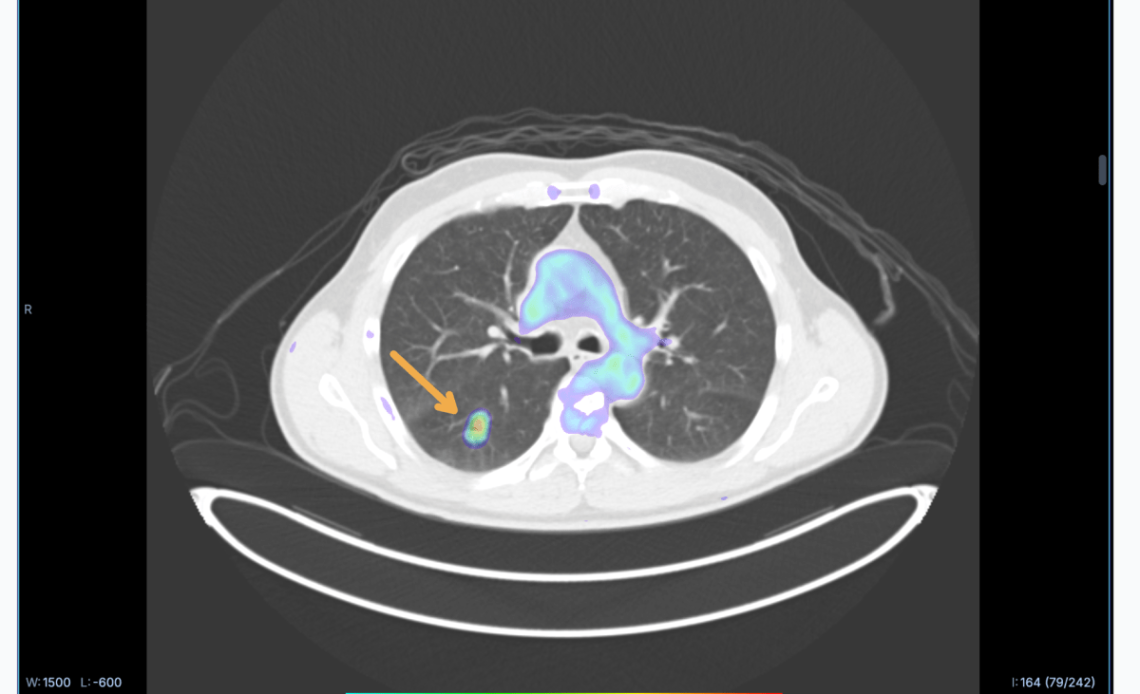

But what if you could use AI to convert CT scans, which are much more accessible and affordable, into PET scans? That’s the pitch of RADiCAIT, an Oxford spinout that came out of stealth this month with $1.7 million in pre-seed financing. The Boston-based startup, which is a Top 20 finalist in Startup Battlefield at TechCrunch Disrupt 2025, has just opened a $5 million raise to advance its clinical trials.

The model learns by comparing CT and PET scans, mapping them, and picking out patterns in how they relate to each other. Sina Shahandeh, RADiCAIT’s chief technologist, describes it as connecting “distinct physical phenomena” by translating anatomical structure into physiological function. Then the model is directed to pay extra attention to specific features or aspects of the scans, like certain types of tissue or abnormalities. This focused learning is repeated many times with many different examples, so the model can identify which patterns are clinically important.

Walsh claims the team at RADiCAIT can mathematically prove that their synthetic or generated PET images are statistically similar to real chemical PET scans.

“That’s what our trials show,” he said, “that the same quality of decision has been made when the doctor, radiologist, or oncologist is given a chemical PET or [our AI-generated PET].”